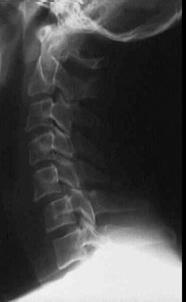

TRAUMA CERVICALA

Incidenta laterala Incidenta

laterala Incidenta

Incidenta oblica Incidenta laterala Incidenta antero-posterioara

Aspect normal Aspect normal Aspect normal